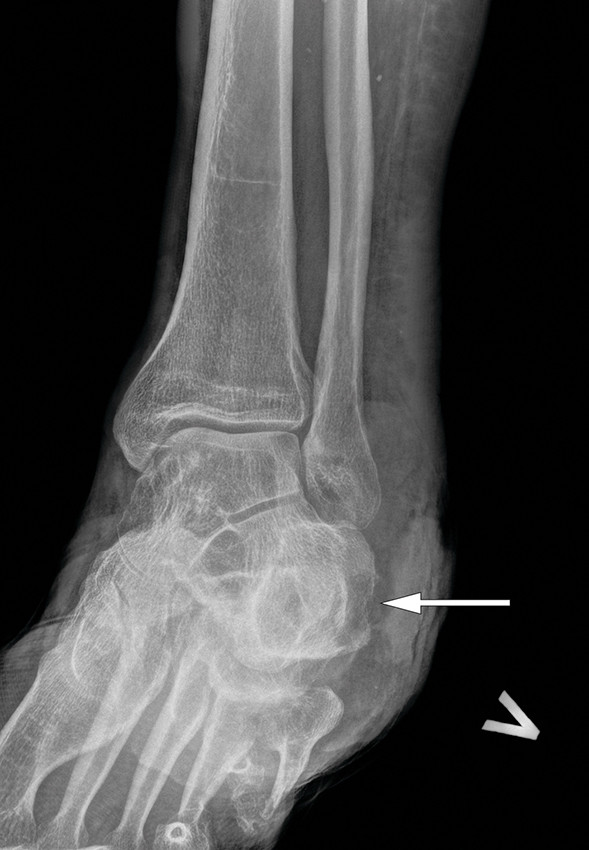

Røntgenbilde av bakre del av foten viste osteolyse (Figur 3), og magnetisk resonanstomografi viste uttalte bløtdelsforandringer og funn forenlig med osteomyelitt i kalkaneus med margødem i storparten av knokkelen og osteolyse baktil (Figur 4). Begge bildeundersøkelsene viste en noe deformert kalkaneus som sannsynlig fraktursekvele. Som metastaseutredning ble det gjort ultralydundersøkelse av regionale lymfeknuter, som viste normale lymfeknuter med upåfallende størrelse, ekko og dopplersignal. Med bakgrunn i funn av osteomyelitt ble pasienten henvist til ortoped for benbiopsi til mikrobiologisk undersøkelse. Denne viste ingen vekst av aerobe bakterier, men anaerob dyrkning viste sparsom vekst av Anaerococcus species, Dialister micraerophilus samt rik vekst av Actinomyces turicencis som var sensitv for klindamycin, meropenem, piperacillin/tazobactam, og penicillin G, men resistent for metronidazol. Funnet ble vurdert ved infeksjonsmedisinsk avdeling. Oppvekst av blant annet Actinomyces turicensis ville sannsynligvis kreve langvarig antibiotikabehandling hos denne pasienten. Samtidig hadde man fra infeksjonsmedisinsk side lite tro på at man ville komme i mål med antibiotikabehandling alene.

Hos pasienter med malignitetsutvikling i kroniske sår over eksponert benvev, slik som ved dekubitalsår eller på ekstremiteter, anbefales radiologisk utredning for vurdering av eventuell underliggende osteomyelitt. Vanlig røntgenundersøkelse kan vise tegn til periostal reaksjon eller bendestruksjon. Magnetisk resonanstomografi viser hvor mye underliggende vev som er involvert, og kan bidra til vurdering av reseksjonsgrenser ved kirurgisk behandling (20). MR-undersøkelse vil også bidra til å foreta en riktig stadieinndeling av tumor.